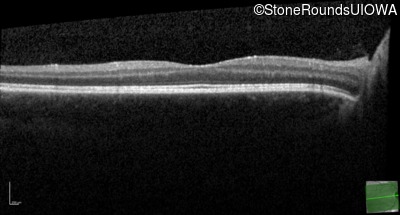

Age at visit: 17 years

OD OS

This 17 year old male had normal vision until about 6 months earlier when he began to lose central vision. The left eye may have been affected prior to the right eye.